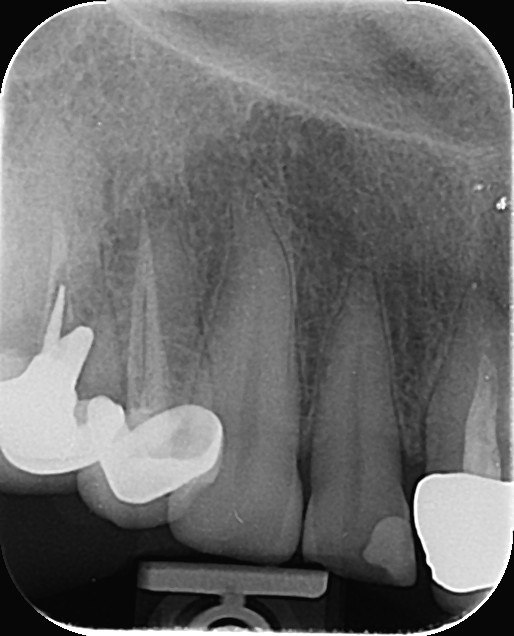

7. What condition can be seen in the tooth # 4.4?

8. What condition can be seen in the distal surface of the tooth # 2.4?

9. What condition can be seen in distal surface of the tooth # 2.6?